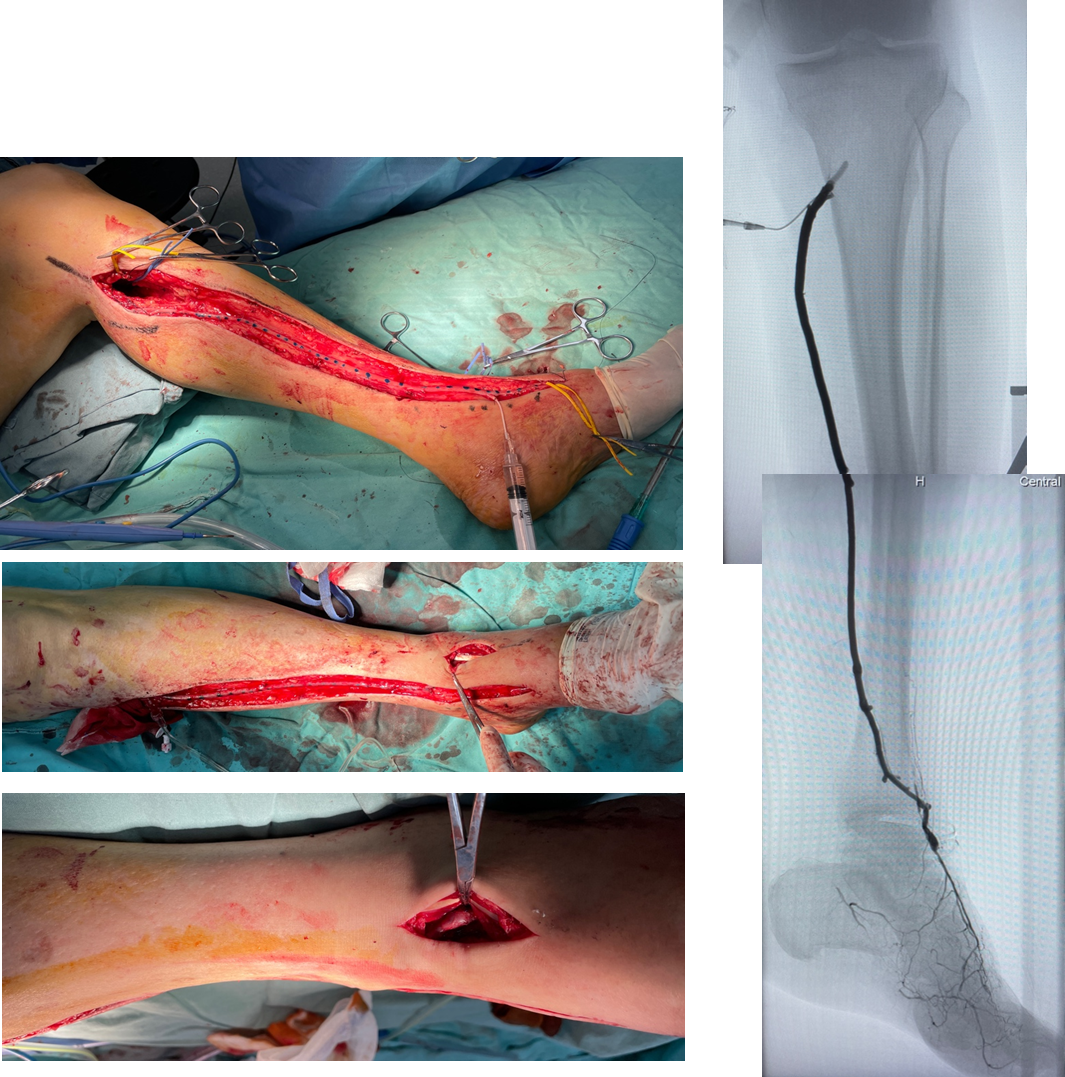

技术失败:R5 ischemia → 股总-远端胫后In-situ GSV旁路

4次EVTs反复复发:R5 ischemia → 腘P3-足背non-reversed GSV旁路

EVT后临床失败:R5 ischemia → 腘P3-足底动脉 reversed GSV旁路

膝上FPAK比例不足10%,在EVT失效病例中,膝下FPBK高达38.9%

两组中,均有高比例远端旁路(踝上及踝下):57% vs 47%

自体静脉使用率:85.34%